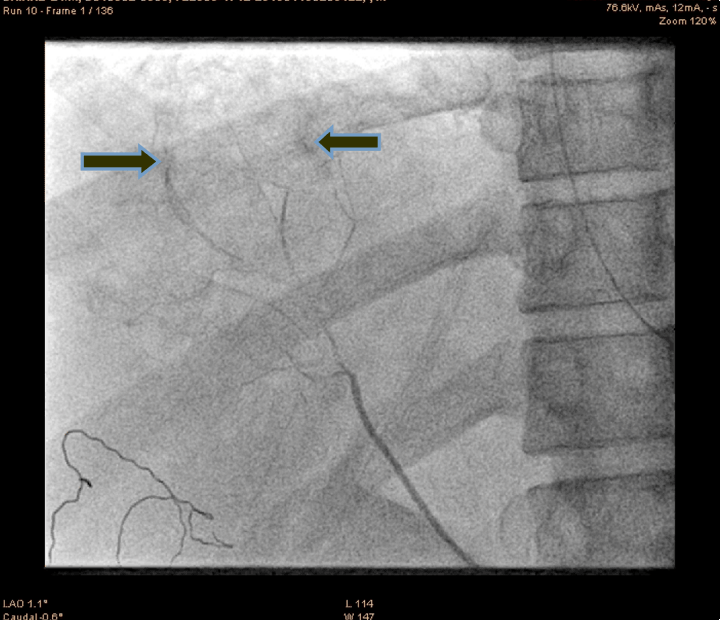

A 21-year-old male presented to the emergency department with alleged history of fall from height of about 10 feet three hours back. The patient was fully conscious and oriented with patent airway and normal breathing and ventilation. On examination, hypotensive (blood pressure 70/50 mmHg), tachycardia (110 bpm) and generalized abdominal tenderness were found. Focused assessment with sonography for trauma (FAST) was positive. So an emergency ultrasonography and contrast-enhanced computed tomography (CECT) scan of the abdomen were done which confirmed significant hemorrhage consistent with a grade III injury by the American Association for the Surgery of Trauma Organ Injury Scale. The patient was resuscitated and shifted to the operation theatre for an exploratory laparotomy, laceration of 4x2 cm with active hemorrhage were noted, the surgeon was not able control the hemorrhage successfully. So the patient was shifted to cath lab. An angiogram of superior mesenteric artery (SMA) showed bleeding from accessory hepatic artery (Figure 1). The diagnostic catheterization of accessory hepatic artery, followed by gel foam infusion to the accessory hepatic artery (Figure 2) and (Figure 3). Figure 4 shows the distal part of accessory hepatic artery occluded. Figure 5 shows occluded right artery following embolization. Repeat arteriography confirmed the occlusion of the vessel. The patient was then transferred to the ICU and transfused one unit of whole blood. He remained hemodynamically stable thereafter, without significant decrease in hematocrit. The patient gradually improved over the next several days and was discharged after two weeks. Follow-up CT scan one month after discharge showed a mild hematoma with no evidence of any infection or complication of the embolization procedure.

Figure 1: Angiogram of superior mesenteric artery showing bleeding from accessory hepatic artery (arrow showing the site of bleed).